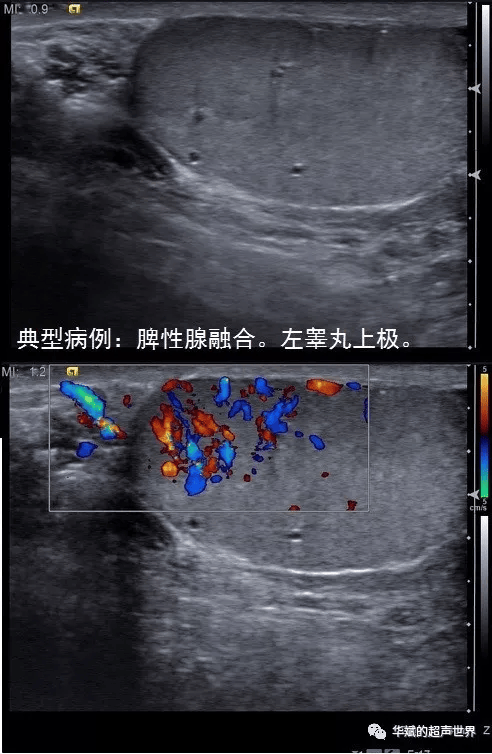

脾性腺融合几乎总是发生在左侧;甲状腺内异位胸腺在左、右两侧的甲状腺中都可以出现。

1. 脾性腺融合:为什么只在左侧?这完全是由胚胎解剖结构决定的。

发生机制:脾性腺融合被认为是脾脏与左侧生殖腺(睾丸或卵巢)在发育过程中发生了短暂的接触和粘连。由于脾脏被限定在左侧,它只能与同样在下降路径中经过左侧的左侧生殖腺发生融合,而无法跨越中线去接触右侧的生殖腺。

因此,脾性腺融合具有绝对的左侧特异性。